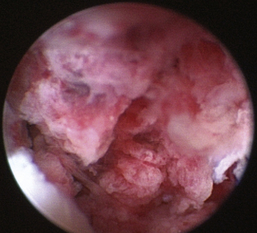

Tumors of the nasal cavity and nasopharynx account for approximately 1% to 2% of all canine and feline neoplasms.1 Benign masses are uncommon. The majority of nasal tumors are malignant, and a variety of germinal origins are reported2,3 (Figures 19-42 through 19-49). Most nasal tumors are primary,2 but metastatic nasal tumors have been reported.3,4 Local infiltration is common. Rostral cerebral metastasis has been reported with a variety of sinonasal tumors.5 Distant metastases of primary nasal tumors are uncommon but have been reported and generally observed later in the disease process.6 Numerous causes have been proposed. Etiologic factors shown to be associated with sinonasal tumor development include exposure to household tobacco smoke,7 coal and kerosene heater exhausts,8 mesaticephaly, and dolichocephaly.9 Generally, complete primary removal of a symptomatic tumor is not possible due to space limitations, sensitivity of local anatomy, and local infiltration by the tumor.9 The prognosis associated with malignant nasal tumors is often poor due to the tumor behavior, inaccessibility of the site to primary treatment, and the significant impact of nasal airflow obstruction on patient quality of life.

image

Figure 19-42 Canine nasal respiratory epithelial adenocarcinoma.

Figure 19-43 Feline nasal adenocarcinoma.

Figure 19-44 Canine solid and acinar nasal adenocarcinoma.

Figure 19-45 Canine nasal neuroendocrine carcinoma.

Figure 19-46 Canine nasal chondrosarcoma.

Figure 19-47 Canine nasal osteosarcoma.

Figure 19-48 Canine undifferentiated nasal spindle cell tumor.

Figure 19-49 Feline high-grade nasal lymphoma.